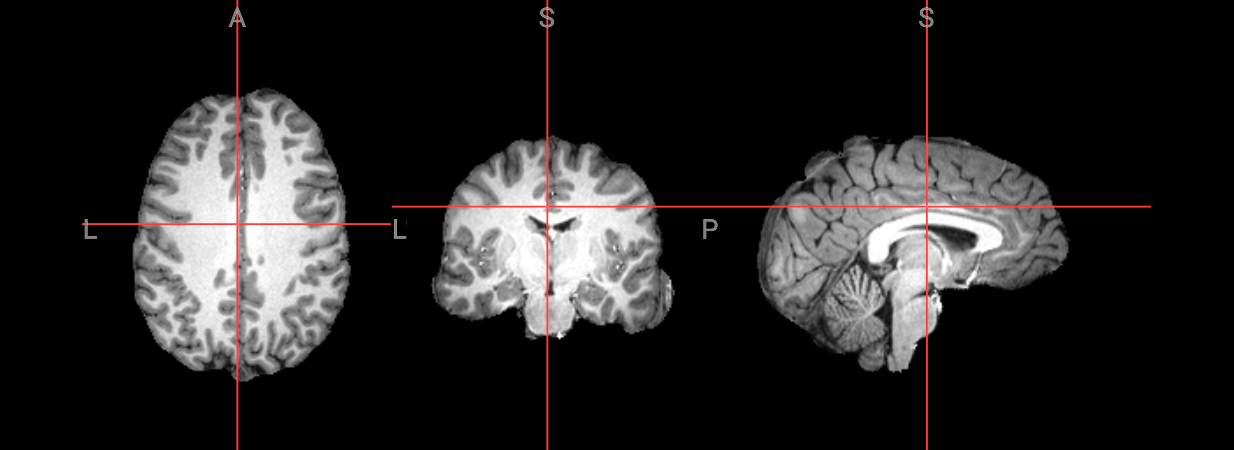

Since fMRI studies focus on brain tissue, our first step is to remove the skull and non-brain areas from the image.

Brain Extraction#

1. ANTs#

First, we will perform brain extraction with this ANTs commands: